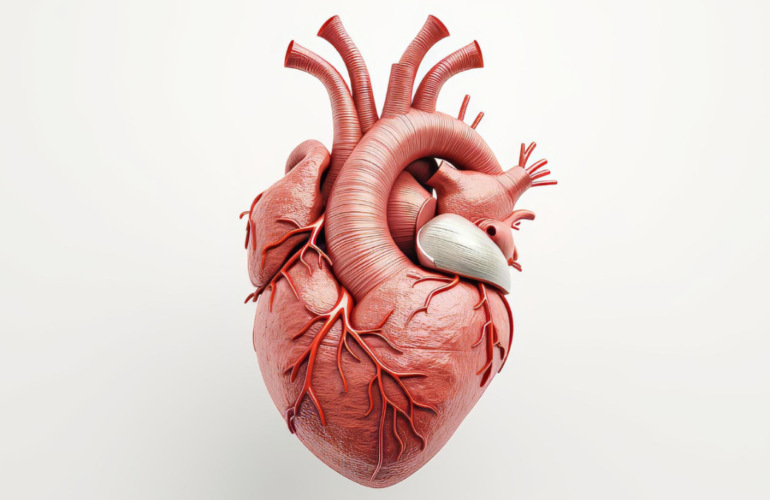

Understanding Heart Conditions and Treatment

Heart disease is a global concern, with common conditions like arrhythmia, coronary artery disease, …

An Introduction to Heart Anatomy and Health

Welcome to Northern Heart Hospital’s blog! Today, we’re diving into the beating…